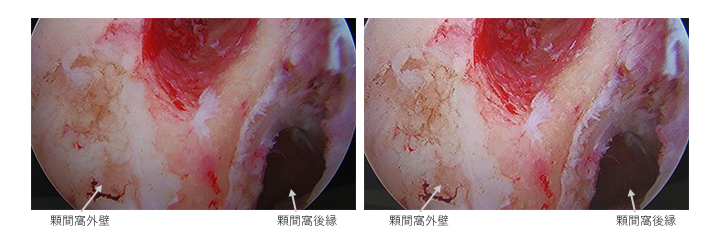

A.I.M.E.機能は、奥行き感や色の再現が優れており、私が知り得たい部位・箇所について、実際に開いて触ってみないと判断できないようなケースでも、画面上で容易に見当がつけられると感じました。肘の症例では、該当組織の切除等の判断時は、限られた関節鏡から得られる情報が非常に重要となります。写真では分かりづらいですが、実際の映像では、境界部分の判断や処置の過程の認識がしやすくなりました。

例えば左の写真のように、手前付近に白い組織があるとそれがハレーションを起こしてしまい、見にくくなってしまうが、A.I.M.E.機能では、ハレーションが抑えられ、確認したい 箇所が見やすくなり、処置がしやすくなったと感じました。

また上の写真では少し分かりづらいですが、組織奥側が暗くて見えづらい場合など、難渋する症例が多いですが、A.I.M.E.画像処理では、奥の深いところも明るく見えました。重要な組織の境界部分の判断や処置方針の決定のための情報が得られやすくなり、即ち術者の手技の効率を高め、処置時間短縮の可能性が期待できそうです。